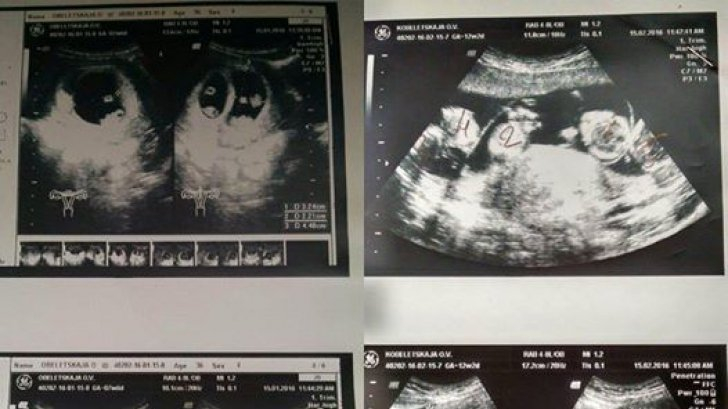

„Totul era ca de obicei: abdomenul gol, gelul și senzorul. Dar când a început să se uite pe ecran, doctorița și-a schimbat expresia feței, iar eu m-am speriat foarte tare” — își amintește Oksana. — „ Îmi amintesc cum ea a început să numere cu voce tare feții, spunând că pentru aceasta ar trebui să mi se ofere o casă pe litoral…”

Nașterea unor cvintupleți fără fertilizare in vitro este un fenomen foarte rar: 1 caz la 55 de milioane. Și în timp ce Oksana încerca să accepte noutatea, medicii discutau entuziasmați despre pacienta lor unică. Majoritatea colegilor lor nu vor vedea așa ceva în întreaga lor viață!